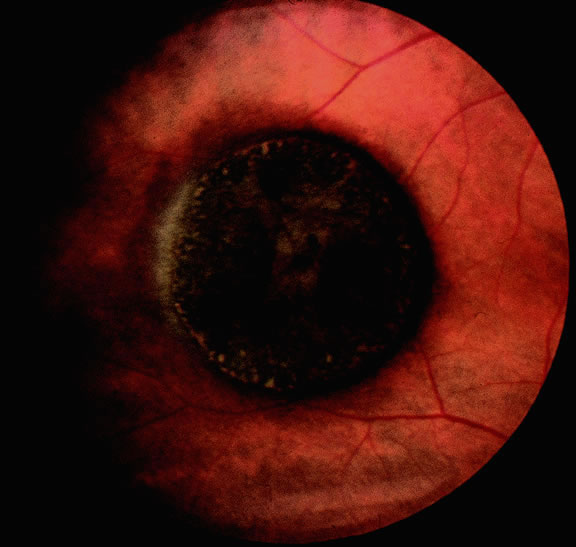

Many choroidal melanomas have a characteristic mushroom or collar button configuration that results when the tumor breaks through Bruch's membrane (Figs. 19, 20, 21, and 22). In such cases there is often secondary choroidal, subretinal, or vitreous hemorrhage. Dilated, intrinsic vessels often are evident in the mushrooming dome of nonpigmented melanomas. The vessels are obscured in more pigmented tumors.48

Fig. 19. Fundus photo of mushroom-shaped choroidal melanoma with nonpigmented dome. Configuration indicates that tumor has ruptured through Bruch's membrane.

Gross Pathology

Choroidal melanomas initially arise in the stroma of the choroid. In early cases, the profile of the sectioned tumor is oval or almond-shaped, and its tissue usually appears relatively cohesive after fixation (Fig. 24). Although some tumors diffusely infiltrate the uvea, most uveal melanomas are relatively well-circumscribed tumors with distinct margins. In many cases the growing melanoma perforates Bruch's membrane and enters the subretinal space where its apex typically assumes a spherical shape that often is likened to a mushroom or collar button (see Figs. 19 to 22.). Dilated vessels often are found in the mushrooming head of the tumor because the ends of Bruch's membrane exert a compressive cinch-like effect on the waist of the tumor (see Fig. 22). Rupture of Bruch's membrane was present in 87.7% of 1527 large- or medium-sized melanomas examined in the COMS.84 Retinal invasion was present in nearly half (49.1%), and tumor cells were found in the vitreous body in one fourth.